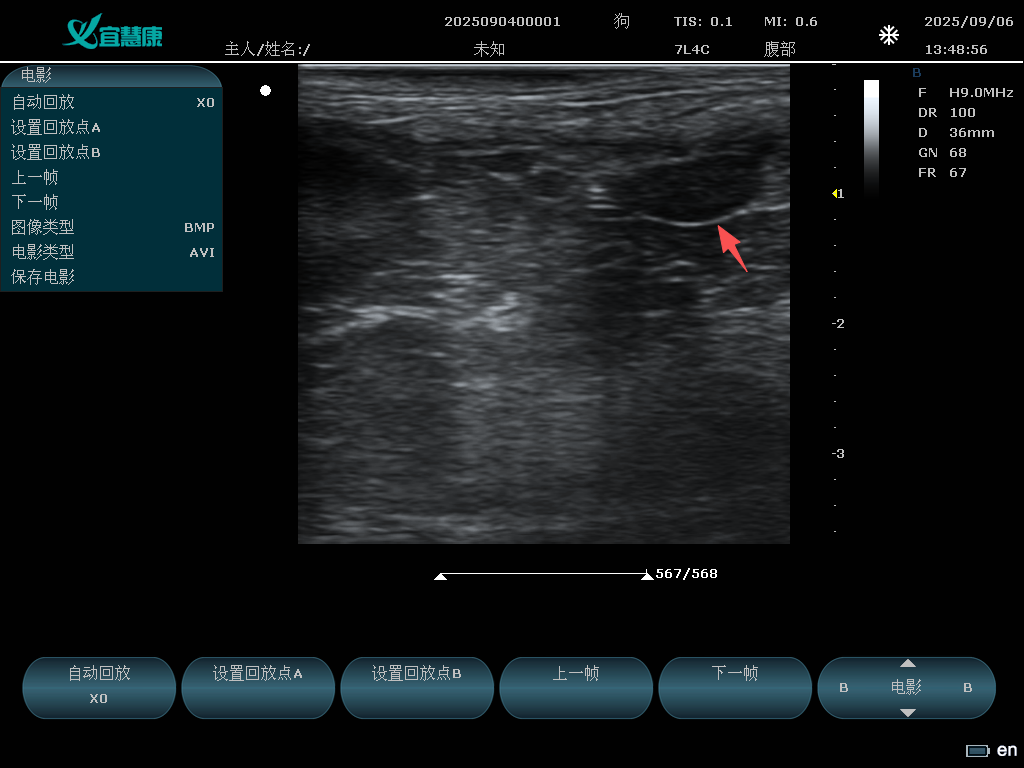

YHK-C90可以用于动物腹部、心脏、产科、小器官、血管、肌腱等方面的检查。支持的动物类型有猫、狗、牛、马、羊 其他。

7L4A: 7.5MHz/L38mm/80阵元线阵探头;

B/M模式:5.0MHz、6.5MHz、7.5 MHz、8.0MHz、 H8.0 MHz 、 8.5 MHz、 H9.0 MHz 、H10.0 MHz

频率:5.0MHz、6.5MHz、7.5 MHz、8.0MHz、 H8.0 MHz 、 8.5 MHz、 H9.0 MHz 、H10.0 MHz